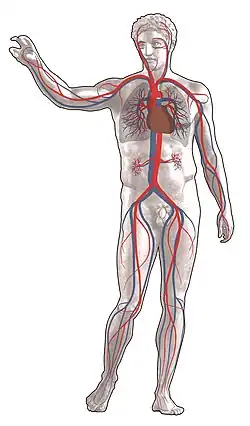

The Circulatory System

The circulatory system is extremely important in sustaining life. It’s proper functioning is responsible for the delivery of oxygen and nutrients to all cells, as well as the removal of carbon dioxide, waste products, maintenance of optimum pH, and the mobility of the elements, proteins and cells, of the immune system. In developed countries, the two leading causes of death, myocardial infarction and stroke are each direct results of an arterial system that has been slowly and progressively compromised by years of deterioration.

The Cardiovascular Pathways

The double circulatory system of blood flow refers to the separate systems of pulmonary circulation and the systemic circulation in amphibians, birds and mammals (including humans.) In contrast, fishes have a single circulation system. For instance, the adult human heart consists of two separated pumps, the right side with the right atrium and ventricle (which pumps deoxygenated blood into the pulmonary circulation), and the left side with the left atrium and ventricle (which pumps oxygenated blood into the systemic circulation). Blood in one circuit has to go through the heart to enter the other circuit. Blood circulates through the body two to three times every minute. In one day, the blood travels a total of 19,000 km (12,000 miles), or four times the distance across the U.S. from coast to coast.

The Pulmonary Circuit

In the pulmonary circuit, blood is pumped to the lungs from the right ventricle of the heart. It is carried to the lungs via pulmonary arteries. At lungs, oxygen in the alveolae diffuses to the capillaries surrounding the alveolae and carbon dioxide inside the blood diffuses to the alveolae. As a result, blood is oxygenated which is then carried to the heart's left half -to the left atrium via pulmonary veins. Oxygen rich blood is prepared for the whole organs and tissues of the body. This is important because mitochondria inside the cells should use oxygen to produce energy from the organic compounds.

The Systemic Circuit

The systemic circuit supplies oxygenated blood to the organ system. Oxygenated blood from the lungs is returned to the left atrium, then the ventricle contracts and pumps blood into the aorta. Systemic arteries split from the aorta and direct blood into the capillaries. Cells consume the oxygen and nutrients and add carbon dioxide, wastes, enzymes and hormones. The veins drain the deoxygenated blood from the capillaries and return the blood to the right atrium.

Homeostasis

Homeostasis in the body is only possible if the cardiovascular system is working properly. This means that the system needs to deliver oxygen and nutrients to the tissue fluid that surrounds the cells and also take away the metabolic waste. The heart is composed of arteries that take blood from the heart, and vessels that return blood to the heart. Blood is pumped by the heart into two circuits: the pulmonary and systemic circuits. The pulmonary circuit carries blood through the lungs where gas exchange occurs and the systemic system transports blood to all parts of the body where exchange with tissue fluid takes place. The cardiovascular system works together with all other systems to maintain homeostasis.